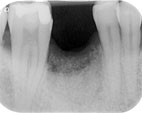

Hier wurde mittels

Smart Grinder (Bild 1) das Zahnfach mit der eigenen

Zahnmasse augmentiert (siehe Rö-Bilder 2 und 3), um

einen stabilen Knochen und genügend Knochensubstanz zu bekommen. Der

horizontale Knochenkamm resorbiert somit nicht und man hat ein ausreichendes

Knochenbett für z.B. ein Implantat (Bild 3).

Bild 2